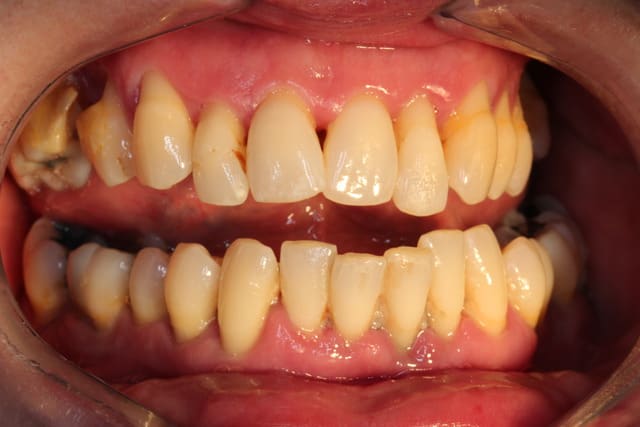

Voici

A toi de juger si la paro peut encore qqch pour cette patiente

A titre purement informatif : mobilité de type II et III de partout ;-)

Il et clair Pp que le cas que tu nous montres est dramatique. D'autant plus dramatique que la solution implantaire ne sera malheureusement pas une solution de long terme.

D'un autre côté, les photos cliniques que tu nous joins montrent clairement que même si la patiente a subi un ttt paro il y a 10 ans, elle n'a en toute certitude pas continuer son traitement de maintenance !

Le traitement des parodontites et d'autant plus quand elles ont un caractère aussi aggressif implique un suivi et traitement régulier du patient. Sans cela, c'est l'échec assuré.

Amicalement

Olivier